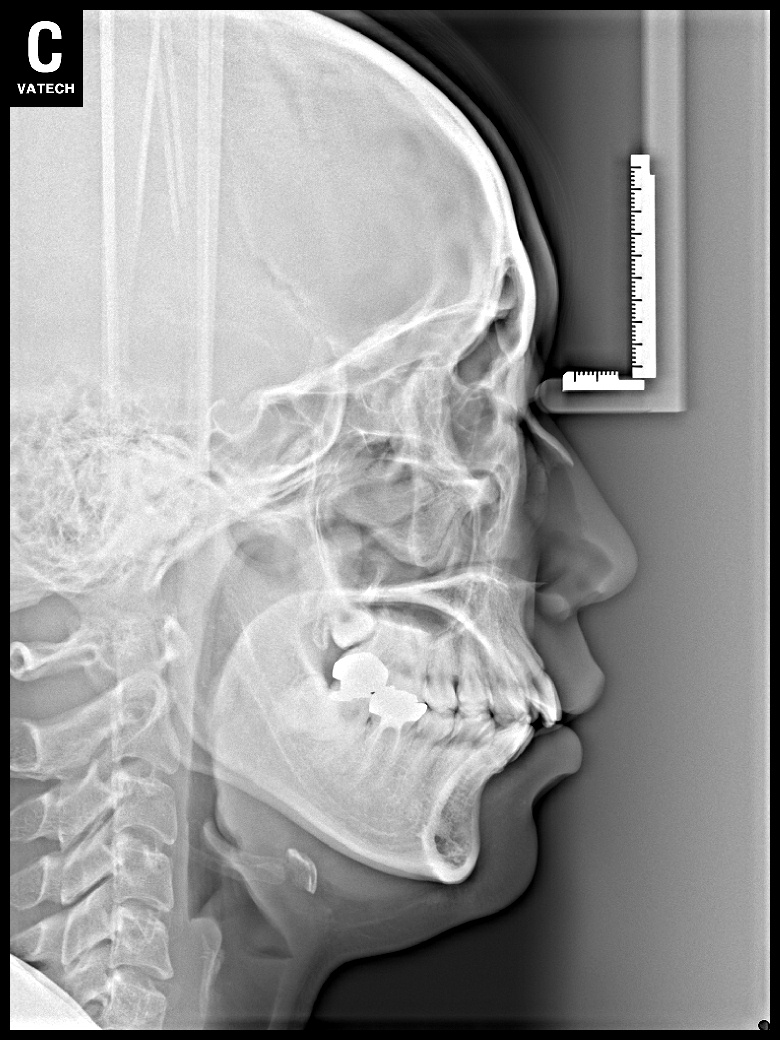

치료 전 사진입니다.